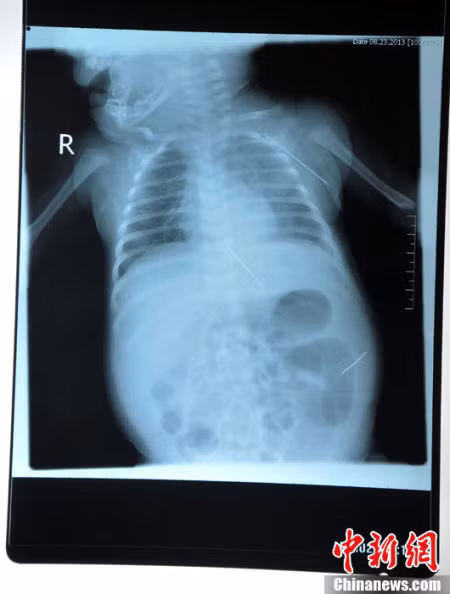

Sau khi được chuyển đến một bệnh viện tại tỉnh Hắc Long Giang, các bác sĩ đã tiến hành chụp X-quang và phát hiện 3 chiếc kim khâu dài khoảng 4,5 cm đâm vào khoang bụng và vùng dưới nách của bé gái.

Ảnh chụp X-quang cho thấy vị trí của chiếc kim khâu.